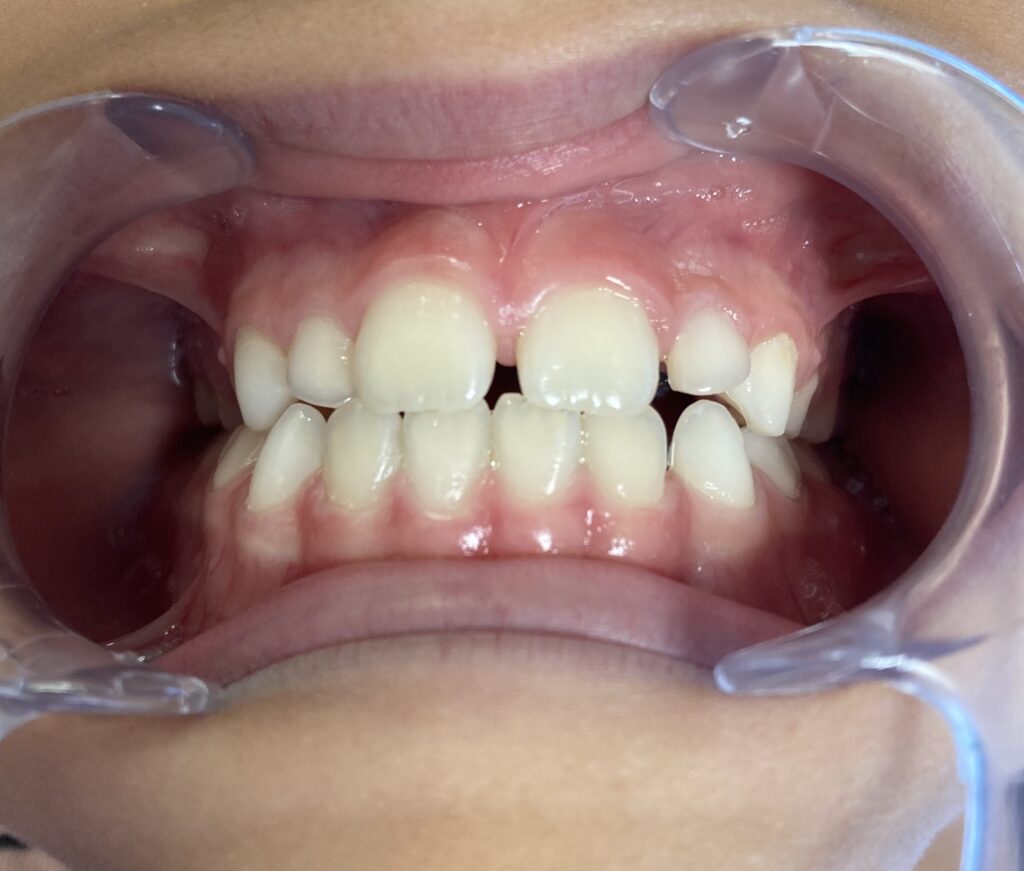

📸 Parfois, une image vaut mieux qu’un long discours…

Voir les photos avant/après sur Instagram : Instagram